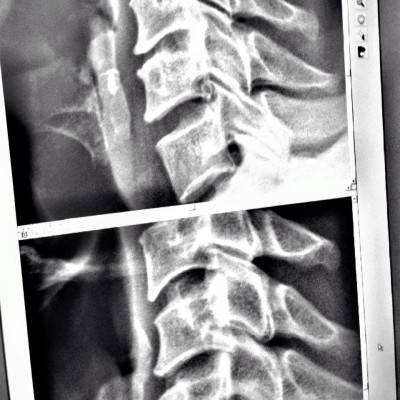

加えて首のヘルニアも2か所…